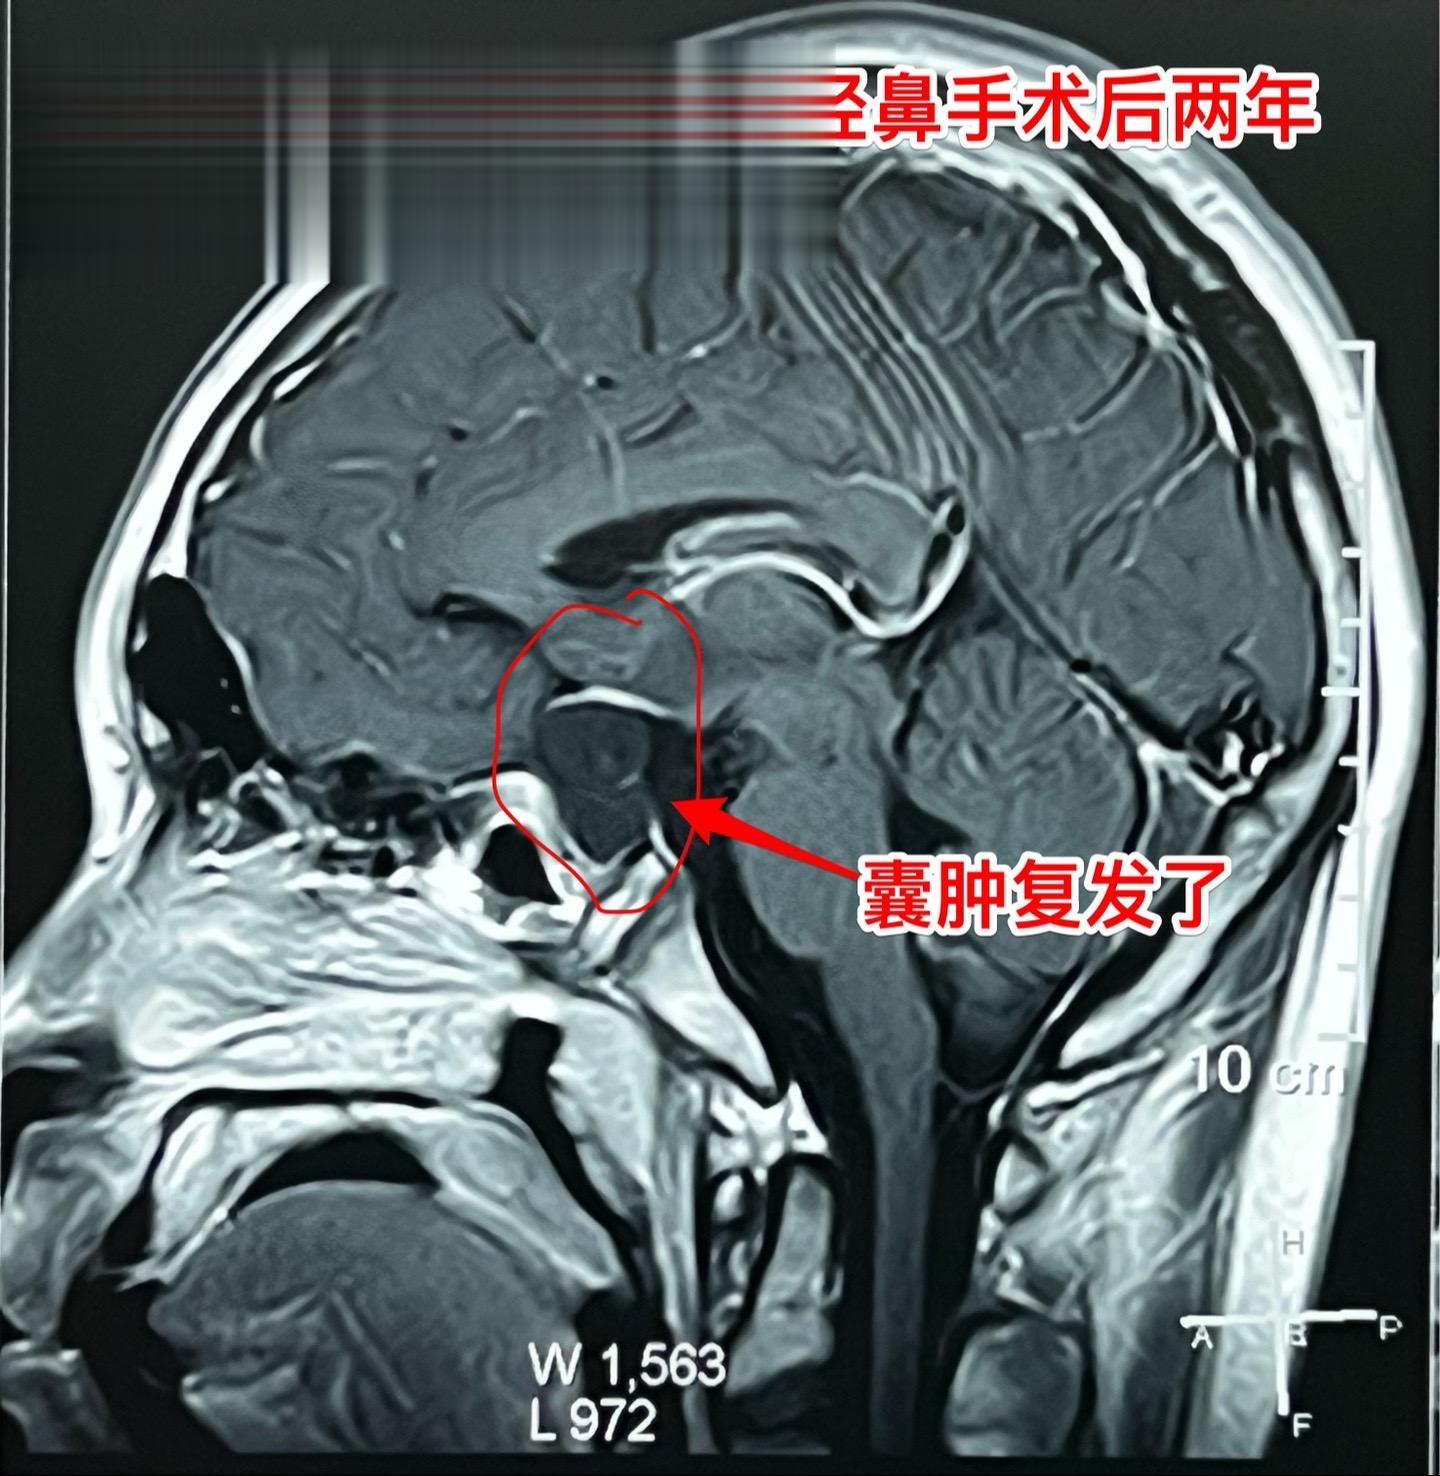

鞍区囊肿不能说是小问题(确诊拉克氏囊肿)16岁的男孩子2年前就因多饮多尿症状到医院检查发现鞍区囊肿,怀疑是拉克氏囊肿。这个病不是真性肿瘤,但是也不是小问题,也会导致尿崩症、生长发育迟缓、视力下降等问题。 他们一家选择了一个著名的医院去作手术,采用经鼻手术方式。遗憾的是手术中取得的标本最终未得出确切的病理诊断。手术后小孩子还出现了脑脊液鼻漏、颅内感染,受老罪了。 随后两年多时间内多次复查磁共振显示囊肿复发了,而且出现视力下降。然而小孩子对于第一次手术的痛苦印象太深了,故而拒绝作第